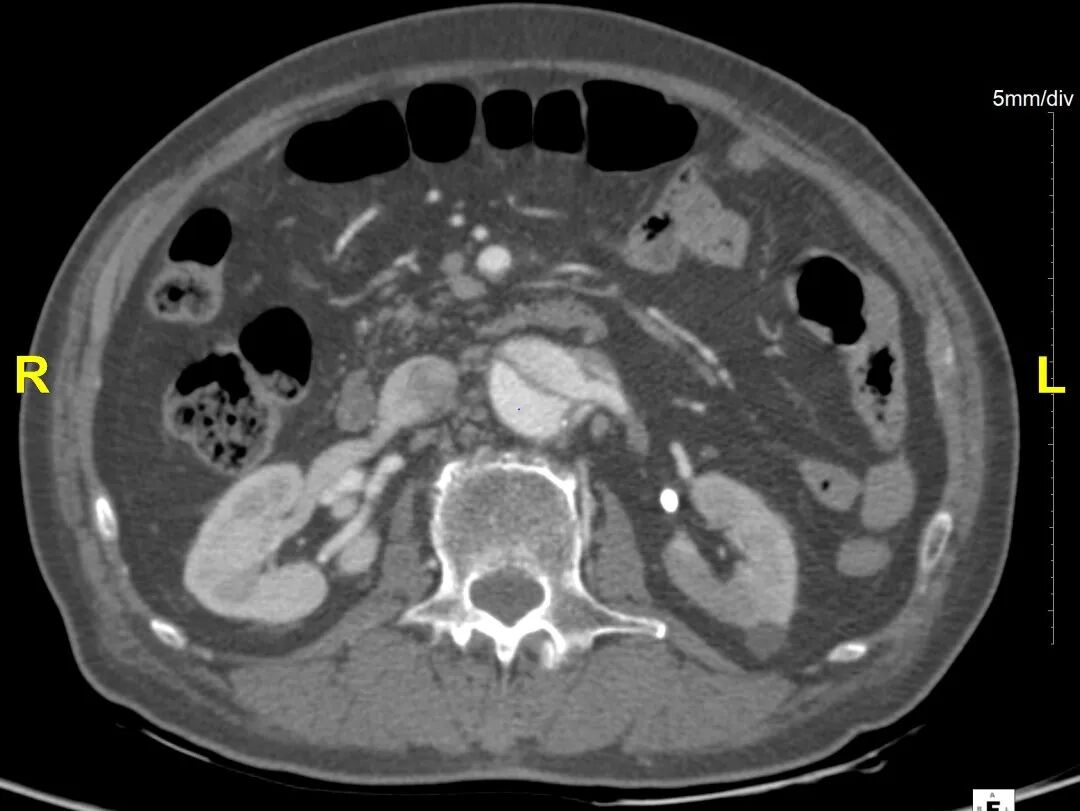

病例CTA详解

横断面影像

1)内膜多处撕裂,真腔严重狭窄。

2)CA假腔供血,SMA双腔供血,LRA假腔供血,RRA真腔供血,腹主段闭塞。